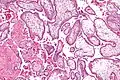

Micrograph showing chorionic villi. Intermediate magnification. H&E stain.